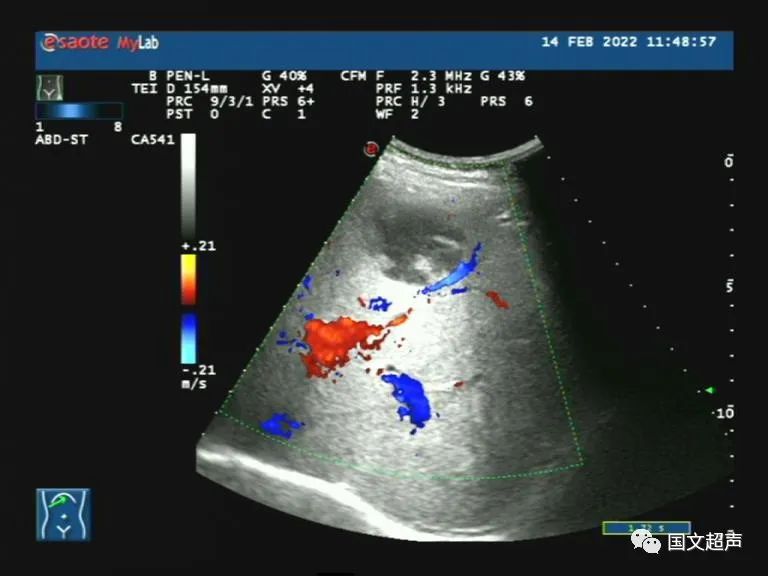

超聲檢查:肝右前葉下段探及混合回聲,形態(tài)尚規(guī)則,邊界較清晰,CDFI:血流信號不明顯。結(jié)合增強CT檢查結(jié)果,考慮肝膿腫,行抗感染及對癥治療。